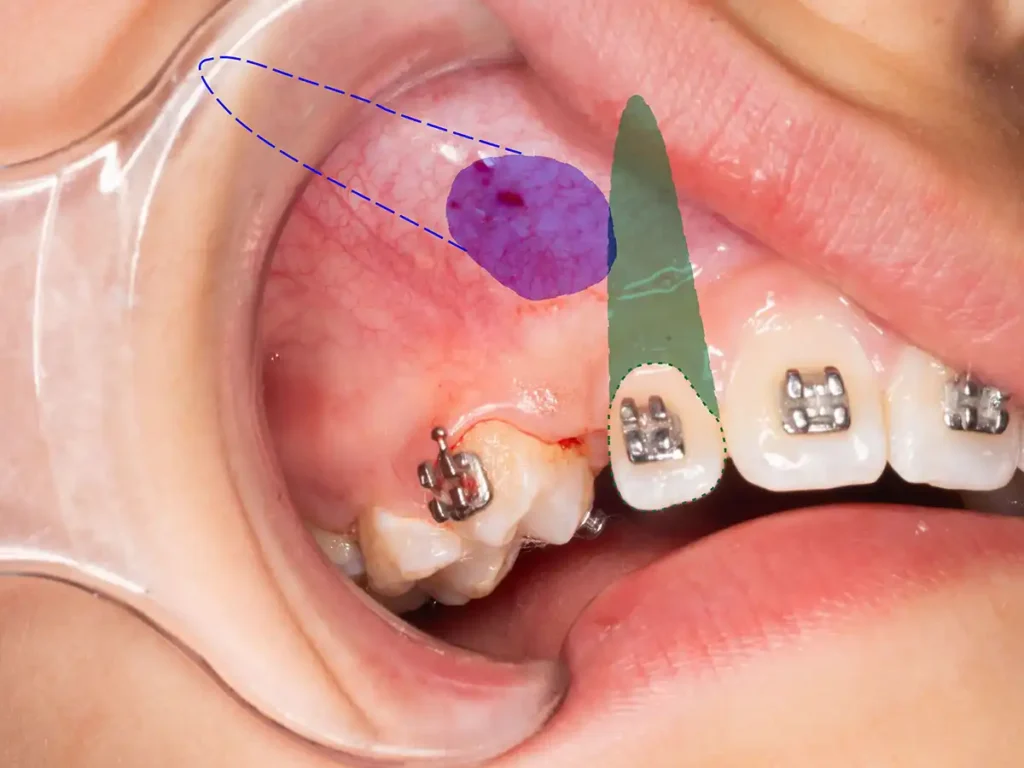

Un canino retenido no es solo un diente que se demoró en erupcionar. Con frecuencia existe una combinación de falta de espacio, alteración en la trayectoria eruptiva y desarrollo maxilar insuficiente. Cuando eso ocurre, el canino puede quedar en una posición profunda o ectópica, comprometiendo su descenso normal y su relación con las raíces vecinas.

En este caso se trató de un paciente de 13 años con alteración de erupción y caninos permanentes retenidos en posición profunda. El análisis clínico y radiográfico permitió confirmar la necesidad de manejo ortodóntico-quirúrgico, junto con una estrategia secuencial para recuperar espacio y mejorar la predictibilidad del tratamiento.

El diagnóstico temprano fue clave. En problemas como el canino retenido, esperar demasiado puede volver más complejo el manejo, aumentar el tiempo total de tratamiento y limitar las opciones de rescate conservador.

El tratamiento de un canino retenido debe decidirse según el desarrollo del paciente, el espacio disponible, la posición del diente y la respuesta esperada al movimiento ortodóntico. No se trata de indicar extracciones de forma automática ni de aplicar una receta estándar.

Lo importante es realizar un diagnóstico serio, establecer etapas claras y controlar la evolución clínica con criterio. En pacientes en crecimiento, actuar a tiempo puede mejorar la predictibilidad y evitar decisiones más invasivas en fases posteriores.